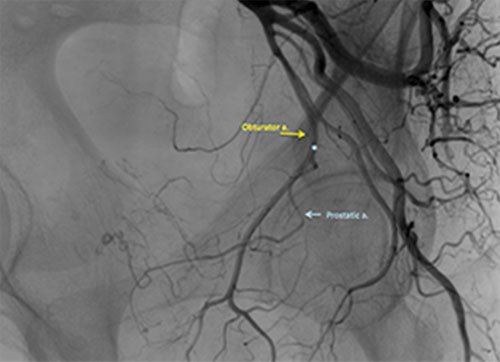

- PAE is performed through a small catheter inserted by your interventional radiologist into the artery in your groin.

- The interventional radiologist will then guide the catheter into the vessels that supply blood to your prostate.

- An arteriogram (an X-ray in which dye is injected into the blood vessels) is done to map the blood vessels feeding your prostate.